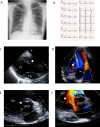

We report a case of ventricular septal defect (VSD) in which we attempted to treat pulmonary arterial hypertension (PAH) with the goal of VSD closure in an adult with suspected Eisenmenger syndrome in childhood. Four years previously (age 41 years), she was referred to our department due to repeated hemoptysis requiring further treatment of PAH. We started combination therapy with several pulmonary vasodilators. Two years later, her pulmonary vascular resistance (PVR) was improved but still not at the level where VSD closure was possible. To control the increased PA flow resulting from intensive PAH treatment and to reduce the risk of hemoptysis, we performed pulmonary artery banding (PAB). As the risk of hemoptysis decreased, a prostacyclin analog was introduced, and the dose was increased. More than 1 year after PAB, active vasoactivity testing became positive, suggesting that the pulmonary vascular lesion was now "reversible". We performed VSD closure and atrial septal defect creation even though her PVR was still high. After the operation, her exercise capacity was remarkably improved. We suggest that stepwise surgical repair with pulmonary vasodilators is an important treatment option for select patients with VSD with severe PAH. <Learning objective: Advances in pulmonary arterial hypertension (PAH) treatment have led to the use of a "treat-and-repair" strategy to close the intracardiac shunt after PAH treatment in select patients with adult congenital heart disease. In our case, ventricular septal defect (VSD) closure was achieved with stepwise surgical repair and a combination of pulmonary vasodilators, even though long-standing severe PAH with persistent hemoptysis remained. Even after a long period of exposure to high blood flow, this strategy may reduce pulmonary vascular resistance and permit eventual closure of the VSD.>.